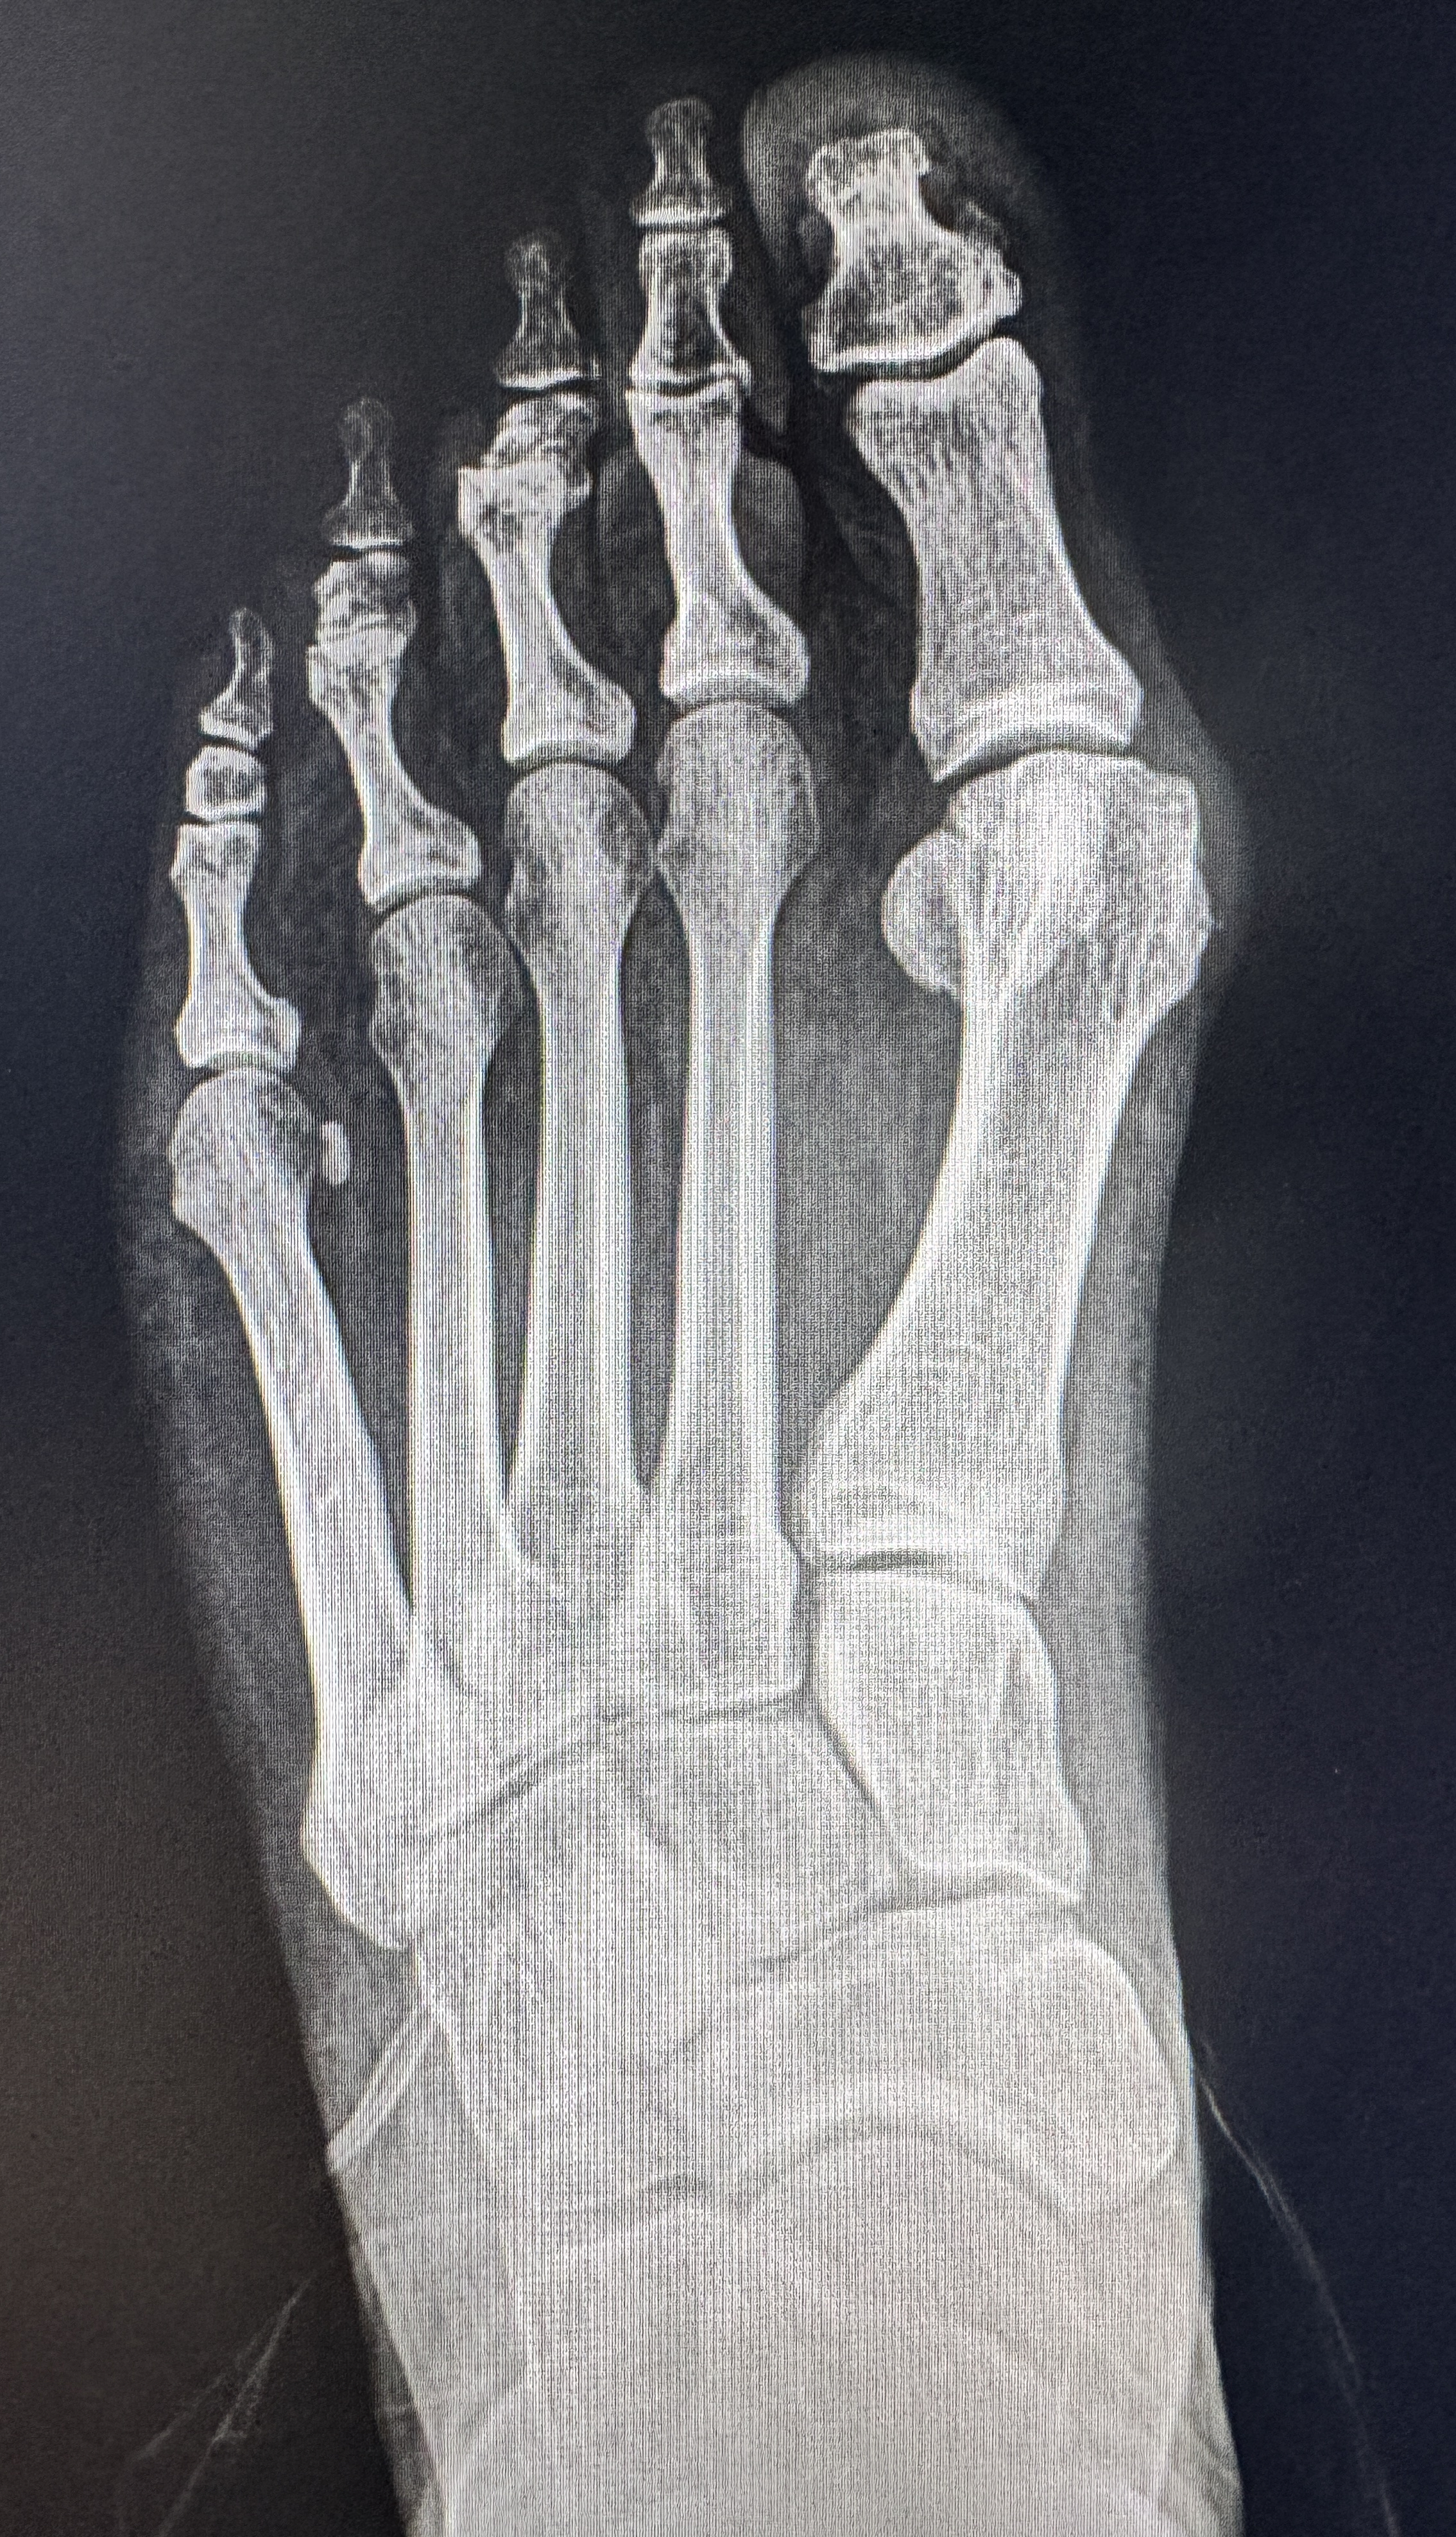

Significant hallux valgus deformity with lateral toe crowding

Excellent realignment — fixation hardware placed through minimal incisions

The following X-rays and clinical photos are from Dr. Bregman's own patients. Note the dramatic bone realignment on X-ray — and on the clinical photos, the incisions are so small they are almost invisible.